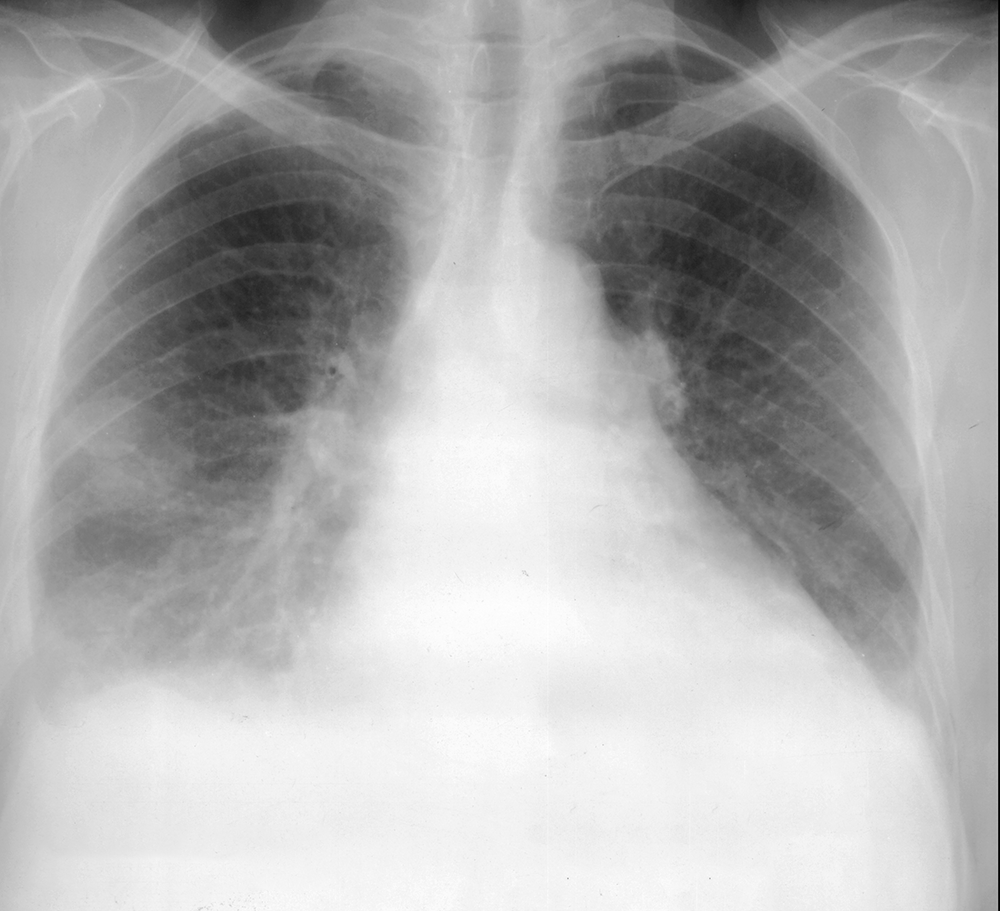

Topic 3

intermediate case for effusion

Further Explanation: